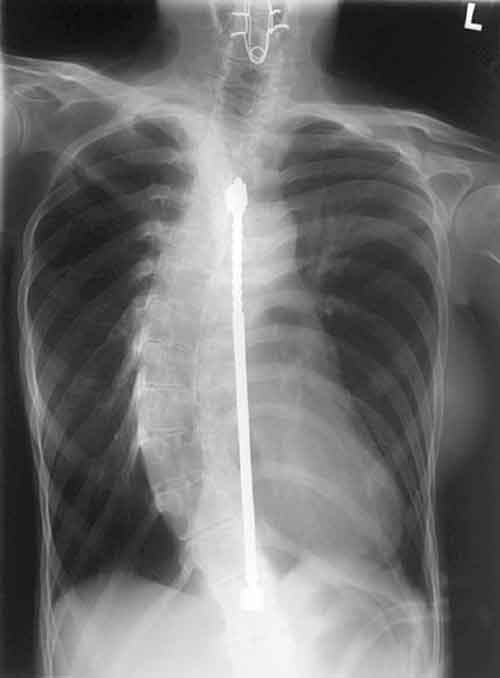

La correzione chirurgica della scoliosi ha assistito negli ultimi anni ad una notevole evoluzione.

“Le moderne procedure – spiega il professore – si basano sull’uso di barre, solitamente in titanio o in acciaio , precedentemente sagomate al fine di riprodurre la curvatura fisiologica del rachide, fissate prevalentemente mediante viti al rachide. Il loro utilizzo permette di ottenere una correzione immediatamente stabile, senza la necessità di ricorrere a corsetti /tutori o busti gessati nella fase post-operatoria. Il paziente può, infatti, alzarsi dopo tre-quattro giorni dall’intervento senza il sostegno di un busto ortopedico, riprendendo a svolgere gradualmente qualsiasi attività”.